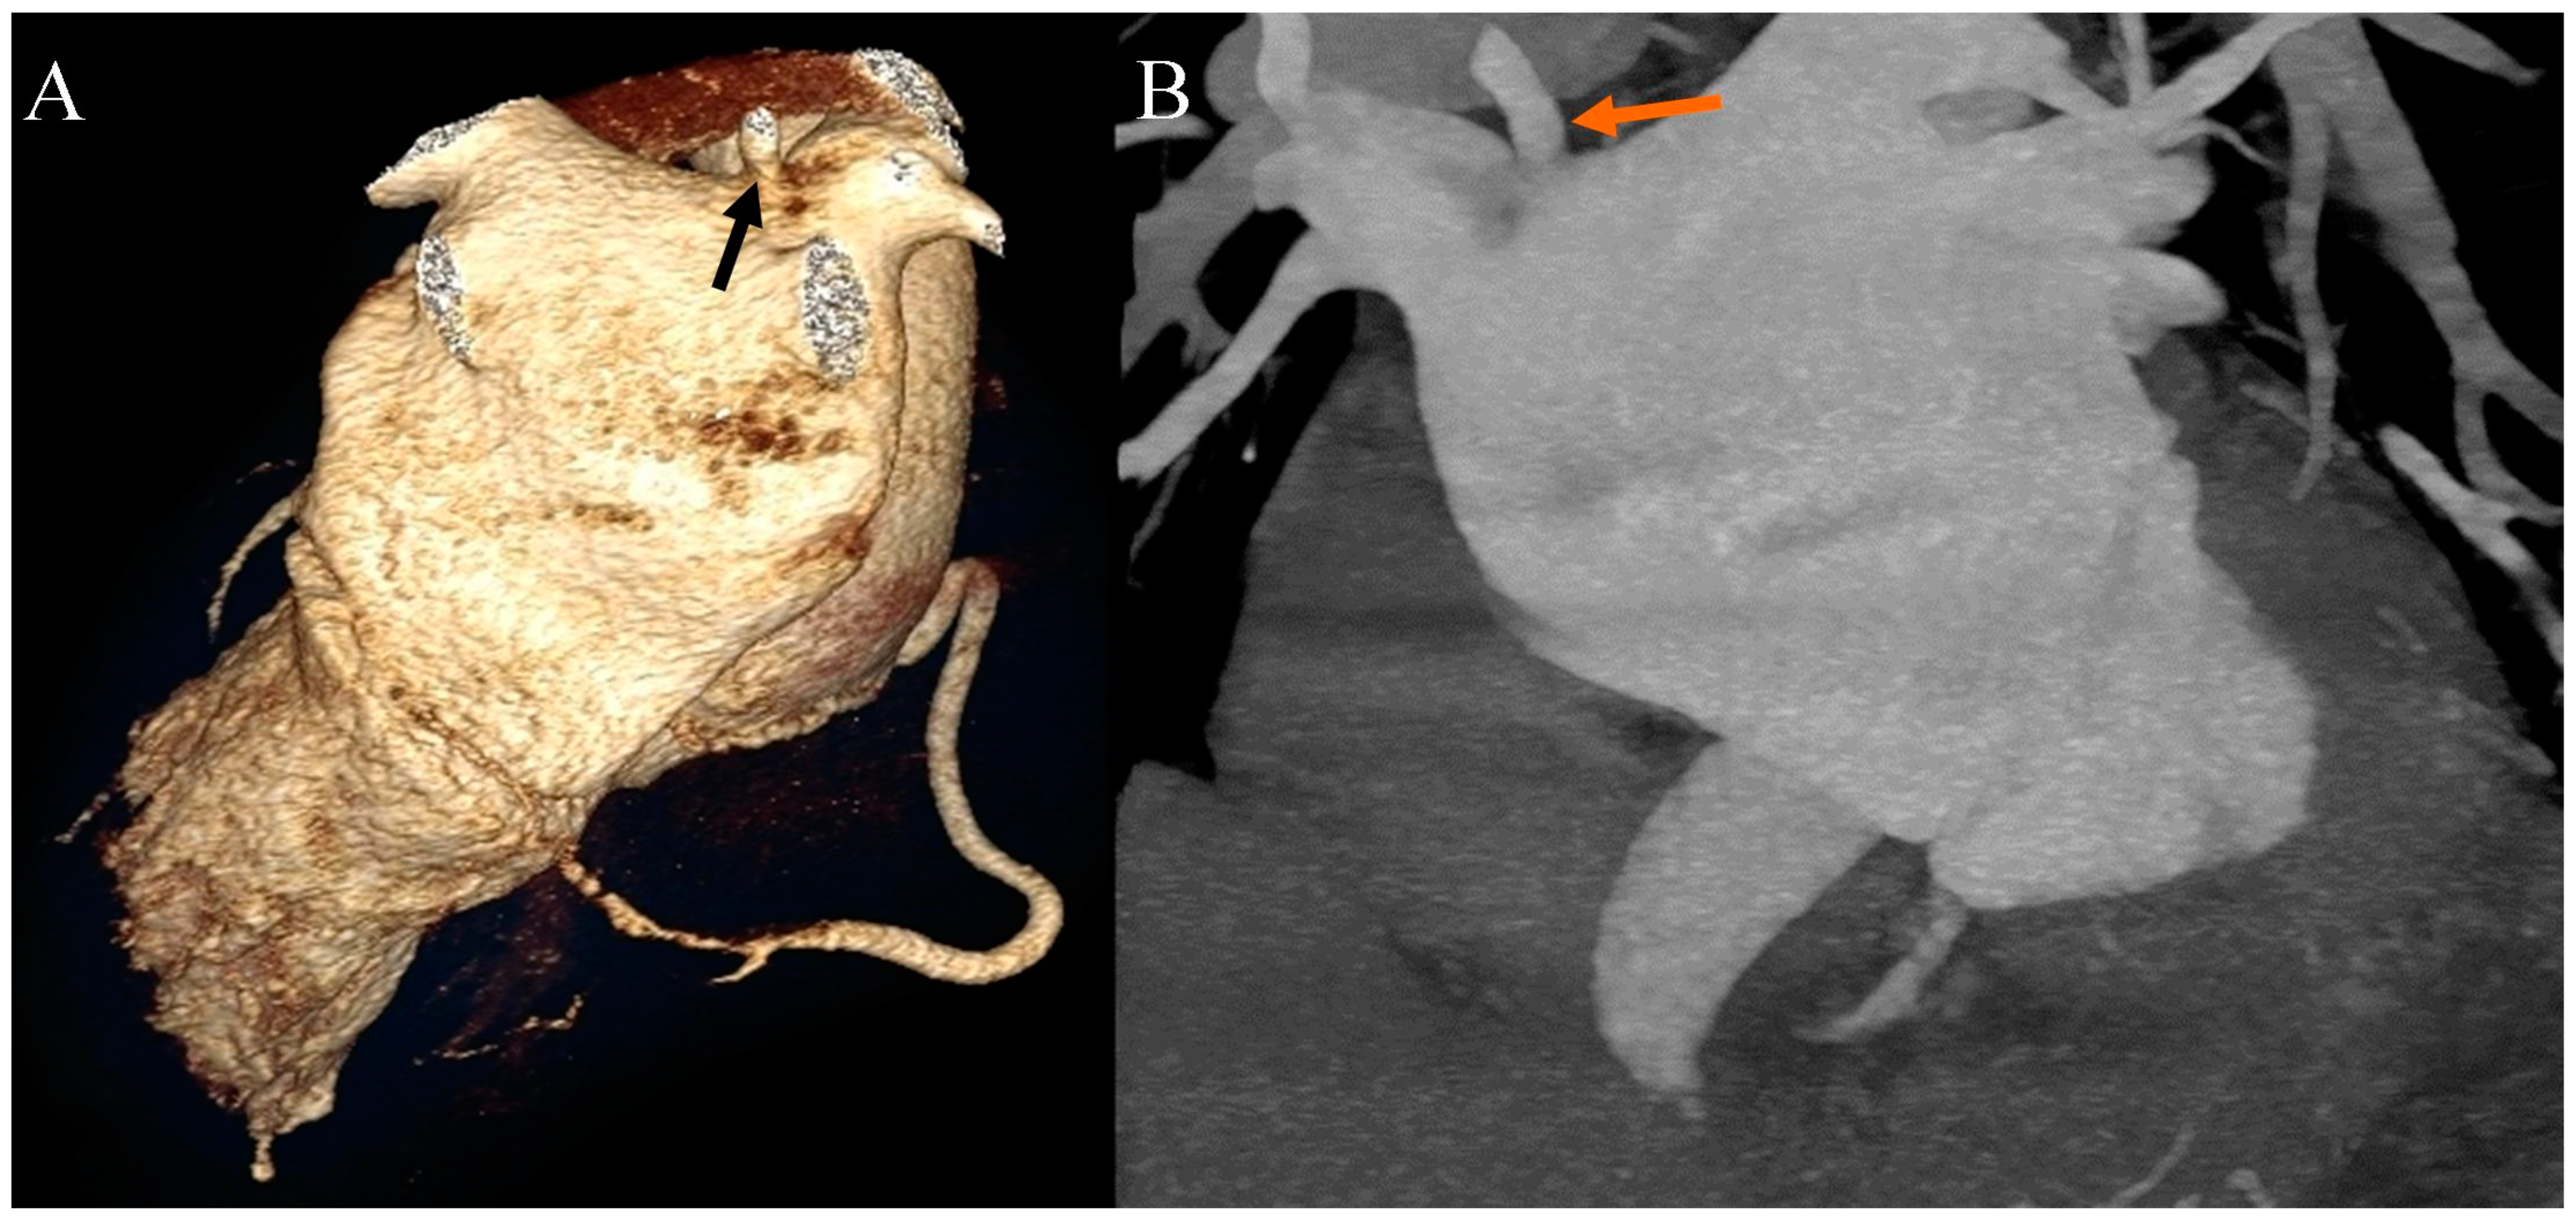

Figure 4.

Coronary artery computed tomography angiography. Accessory right pulmonary vein. (A) Volume-rendering technique reconstruction. Posterior view. The arrow indicates the accessory right pulmonary vein on the upper wall of the left atrium. (B) Maximum intensity projection reconstruction. Anterior view. The arrow indicates the accessory right pulmonary vein on the upper wall of the left atrium.